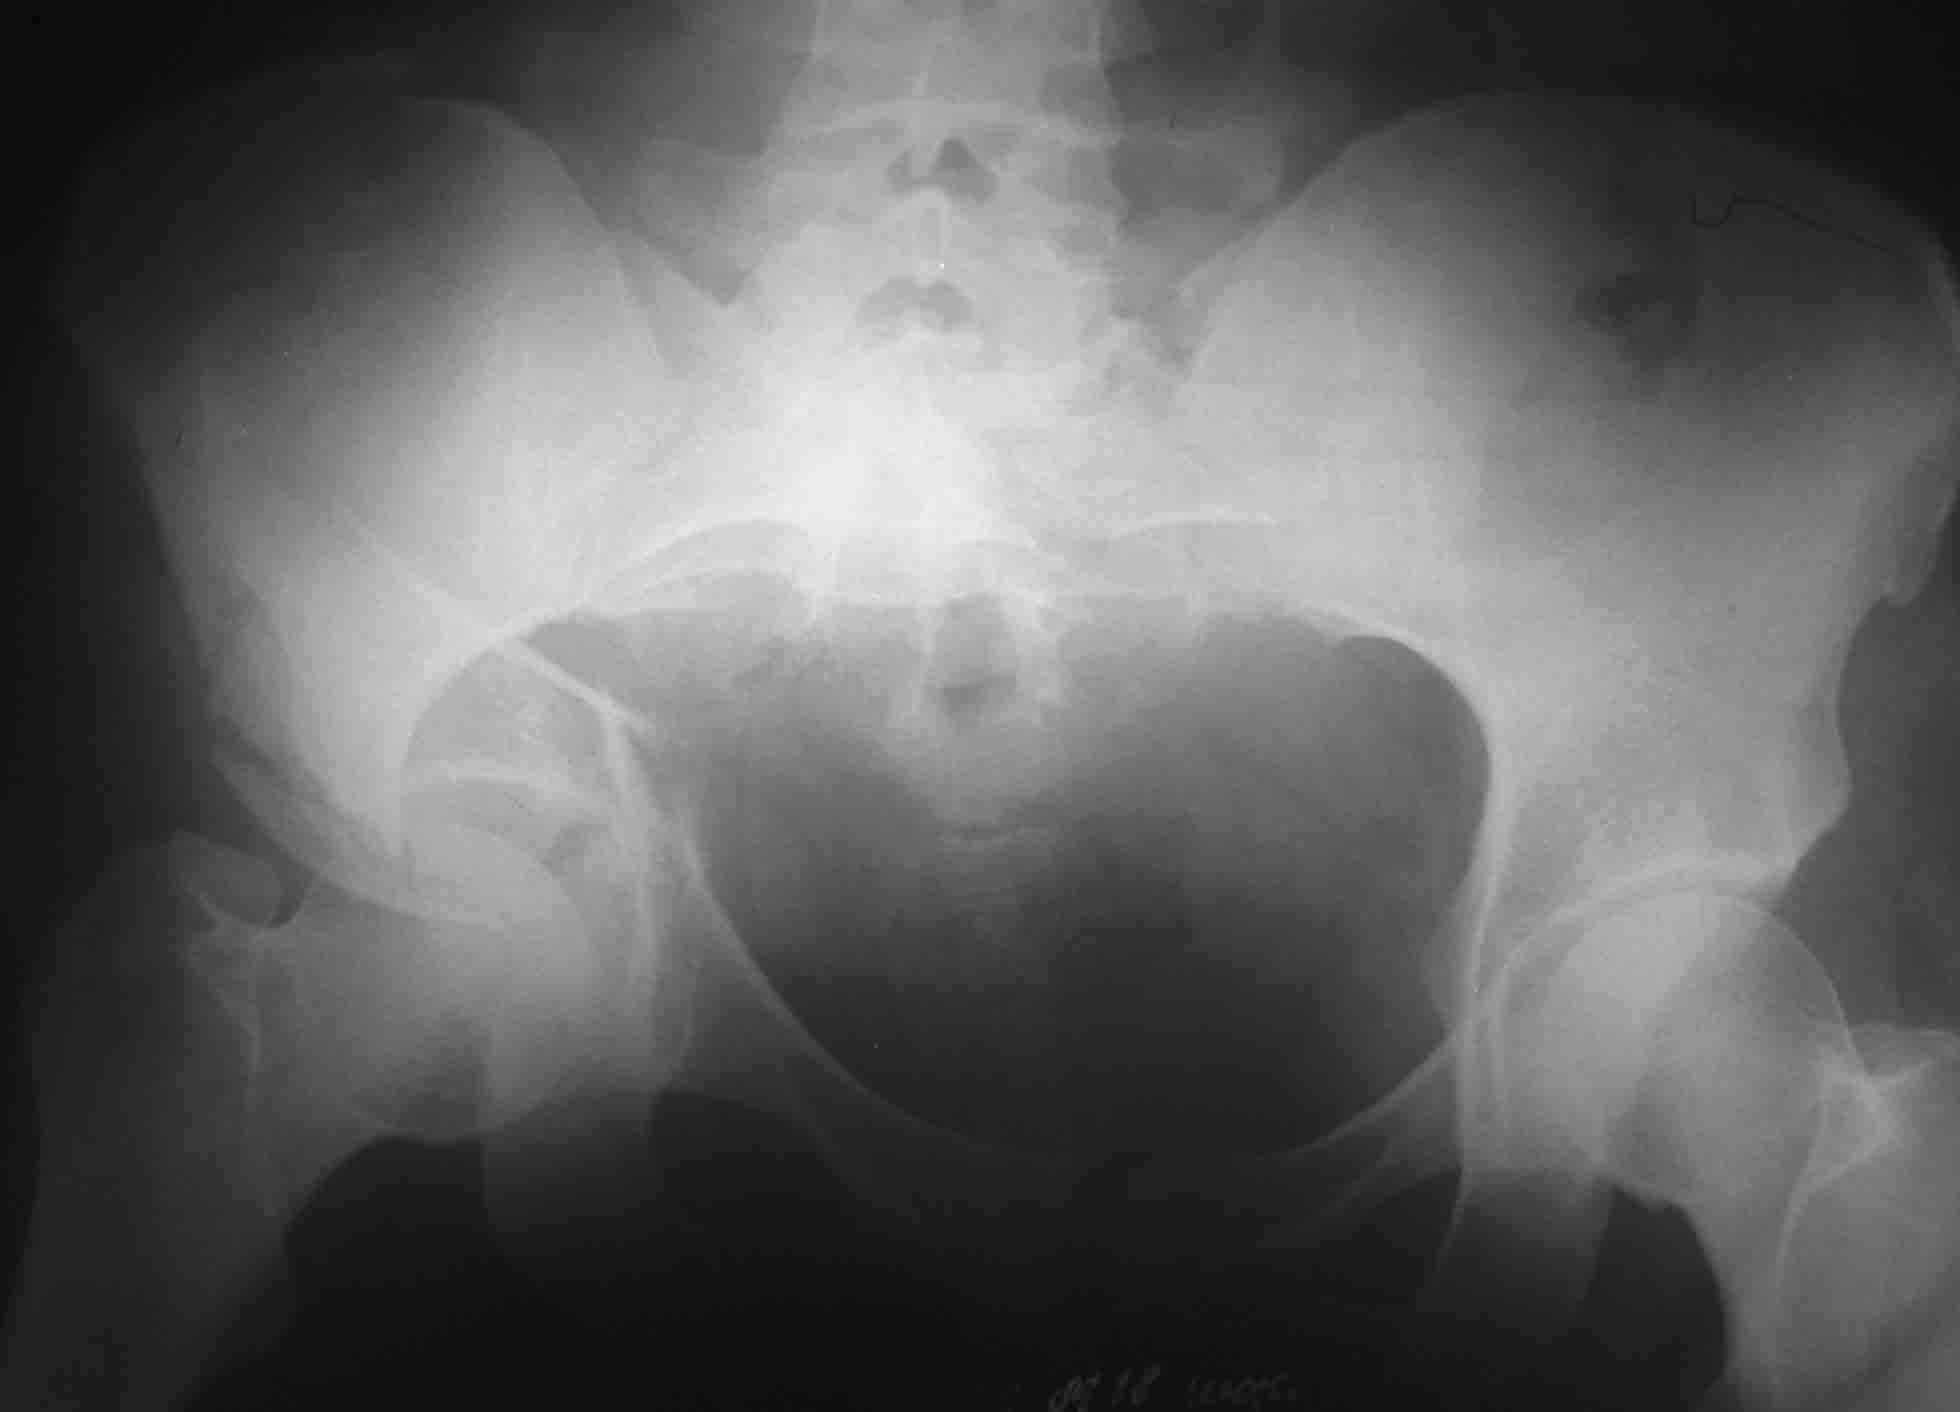

Пациентка 26 лет поступила в больницу 9 дней назад после кататравмы (падение с 4-го этажа)Тяжелая сочетанная травма: Ушиб головного мозга средней тяжести.З/полифокальный перелом таза (оскольчатый чрезвертлужный справа, латеральной массы крестца слева со смещением отломков. З/оскольчатый перелом н/3 правого бедра. З/оскольчатый перелом правой пяточной кости. Тупая травма живота - разрыв слизистой толст кишечника, кисты яичника.

При поступлении - лапаротомия, ушивание ран кишечника, резекция кисты; скелетное вытяжение за правую н/конечность (бугрист б/б кости) На 2-й день на таз наложен стержневой аппарат из "того что было" (по паре стержней в подвздош кости) - естественно, при таком переломе фиксации таким аппартом практически никакой. Пациентка 2 дня назад переведена из реанимации в травм отделение, состояние средней тяжести, показатели красной крови - эритр 2,7; Гб - 75 г/л; Спицевое вытяжение за б/вертел не накладывали из-за возможности инфицирования бедра (пациенка по комплекции довольно упитанная)Встает вопрос - что и в какой последовательности делать с поврежденными сегментами скелета? Думали о варианте: Первым этапом - погружной остеосинтез бедра (DCS? интерлокинг?)и ,возможно, пяточной кости.Вторым этапом - стержневой остеосинтез таза с бедренным модулем (внутренний остеосинтез таза, думаю, по соматике пациентки будет возможен не скоро)

Первым этапом штифтование бедра, лучше длинная Gamma, чко пяточной кости в максимально простой комплектацией (с пяткой можно будет разобраться позже, результат все равно будет "не очень", так что, скорее всего, дело закончится артродезом), вытяжение за мыщелки бедра 12-15 кг. Вторым этапом (максимально рано, насколько это возможно) внутренний остеосинтез вертлужной впадины (планирование и выполнение доступов можно посмотреть на http://odoc.ru/art_cont.php. Похоже, что вы имеете дело с низким двухколонным переломом, для уточнения необходимы проекции Judet.

Закрытая репозиция в таких случаях маловероятна - сохранится дисконгруэнтность. В вертел ничего вводить не надо. аппарат на тазу не нужен, лучше убрать, если вы не намерены наладить автономное скелетное вытяжение (таз-бедро), т.к. импрессионные переломы крестца в III зоне достаточно стабильны, а внешняя железяка может ограничить вас при планировании доступов.

Разве перелом крестца компрессионный, а расхождение, а вертикальное смещение?

И обратите внимание на подозрительную ступень на уровне левой подвздошной кости (перелом крыла с образованием треугольного фрагмента?).

Может это билатеральное повреждение таза, причем нестабильное с обеих сторон, + двухколонный перелом вертлужной впадины с задним краем?